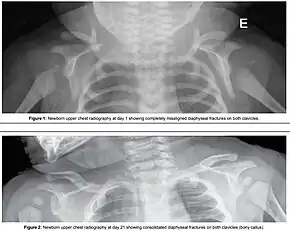

Fracture of both clavicles as a result of shoulder dystocia (top) – Post healing (bottom)

One complication of shoulder dystocia is damage to the upper brachial plexus nerves. These supply the sensory and motor components of the shoulder, arm, and hands. The ventral roots (motor pathway) are most prone to injury. The cause of injury to the baby is debated, but a probable mechanism is manual stretching of the nerves, which in itself can cause injury. Excess tension may physically tear the nerve roots out from the neonatal spinal column, resulting in total dysfunction.